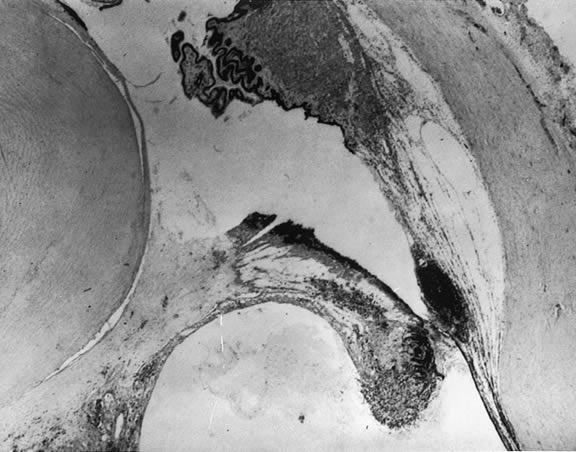

When the vitreous detaches from the area of the optic nerve head, a tag of tissue may be avulsed, and at times a complete ring of peripapillary tissue may come forward with the vitreous. The presence of this ring is pathognomonic for a PVD (Fig. 8). Electron microscopic studies on autopsy eyes with PVDs demonstrate frequent glial epipapillary membranes on the vitreous side of the ILM of the optic nerve and surrounding retina.70,71 There are interruptions in the epipapillary membranes, as well as separations of the membranes from the underlying ILM of the disc, both of which contained incarcerated collagen fibers identical with vitreous fibrils. This intimate association of the vitreous in the disc area accounts for the frequent avulsion of tissue in a PVD. Glial tissue occurs on the posterior hyaloid in 57% of PVDs.

Fig. 8. Gross pathology specimen of an eye of an 85-year-old patient with a posterior vitreous detachment. An epipapillary membrane has been avulsed and is suspended in the posterior hyaloid. The inset shows details of the epipapillary ring. (Foss RY: Anatomic and pathologic aspects of the vitreous body. Trans Am Acad Ophthalmol Otolaryngol 1973;77:171)